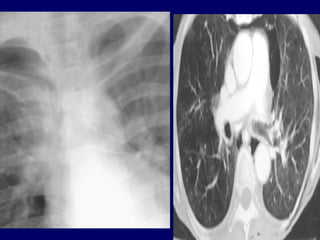

Notice the increased lucency of the cardiophrenic sulci in this patient

with inferior anteromedial pneumothoraces. A CT scan confirms the

diagnosis